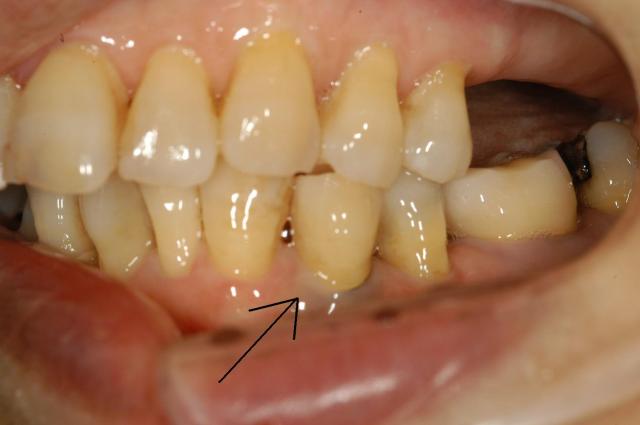

º¸¾å¤Î²èÁü¤ÏÈ´¤±Íî¤Á¤¿¥¤¥ó¥×¥é¥ó¥È¤Ç¡¢´¶À÷¤·¤Æ¤¤¤ë¤â¤Î¤ÏÄˤߤâ¤Ê¤¯¥Ý¥í¥Ã¤ÈÈ´¤±Íî¤Á¤Æ¤¤¤¯¡£

³§¤µ¤ó¤³¤ó¤Ê¤³¤È¤Ë¤Ê¤é¤Ê¤¤¤è¤¦¤ËÀ±Ìî»õ²Ê¶ðÂô¥¯¥ê¥Ë¥Ã¥¯¤Ç¤ÏºÇÁ±¤ÎÊýË¡¤Ç°Â¿´¡¦°ÂÁ´¡¦³Î¼Â¤Ë¼£ÎŤ·¤Þ¤¹¡£

º¸²¼¤¬È´¤±¤ëÁ°¤Î²èÁü

±¦²¼¤¬ºÆÅÙ¿¢Î©¤µ¤ì¤¿¥¤¥ó¥×¥é¥ó¥È